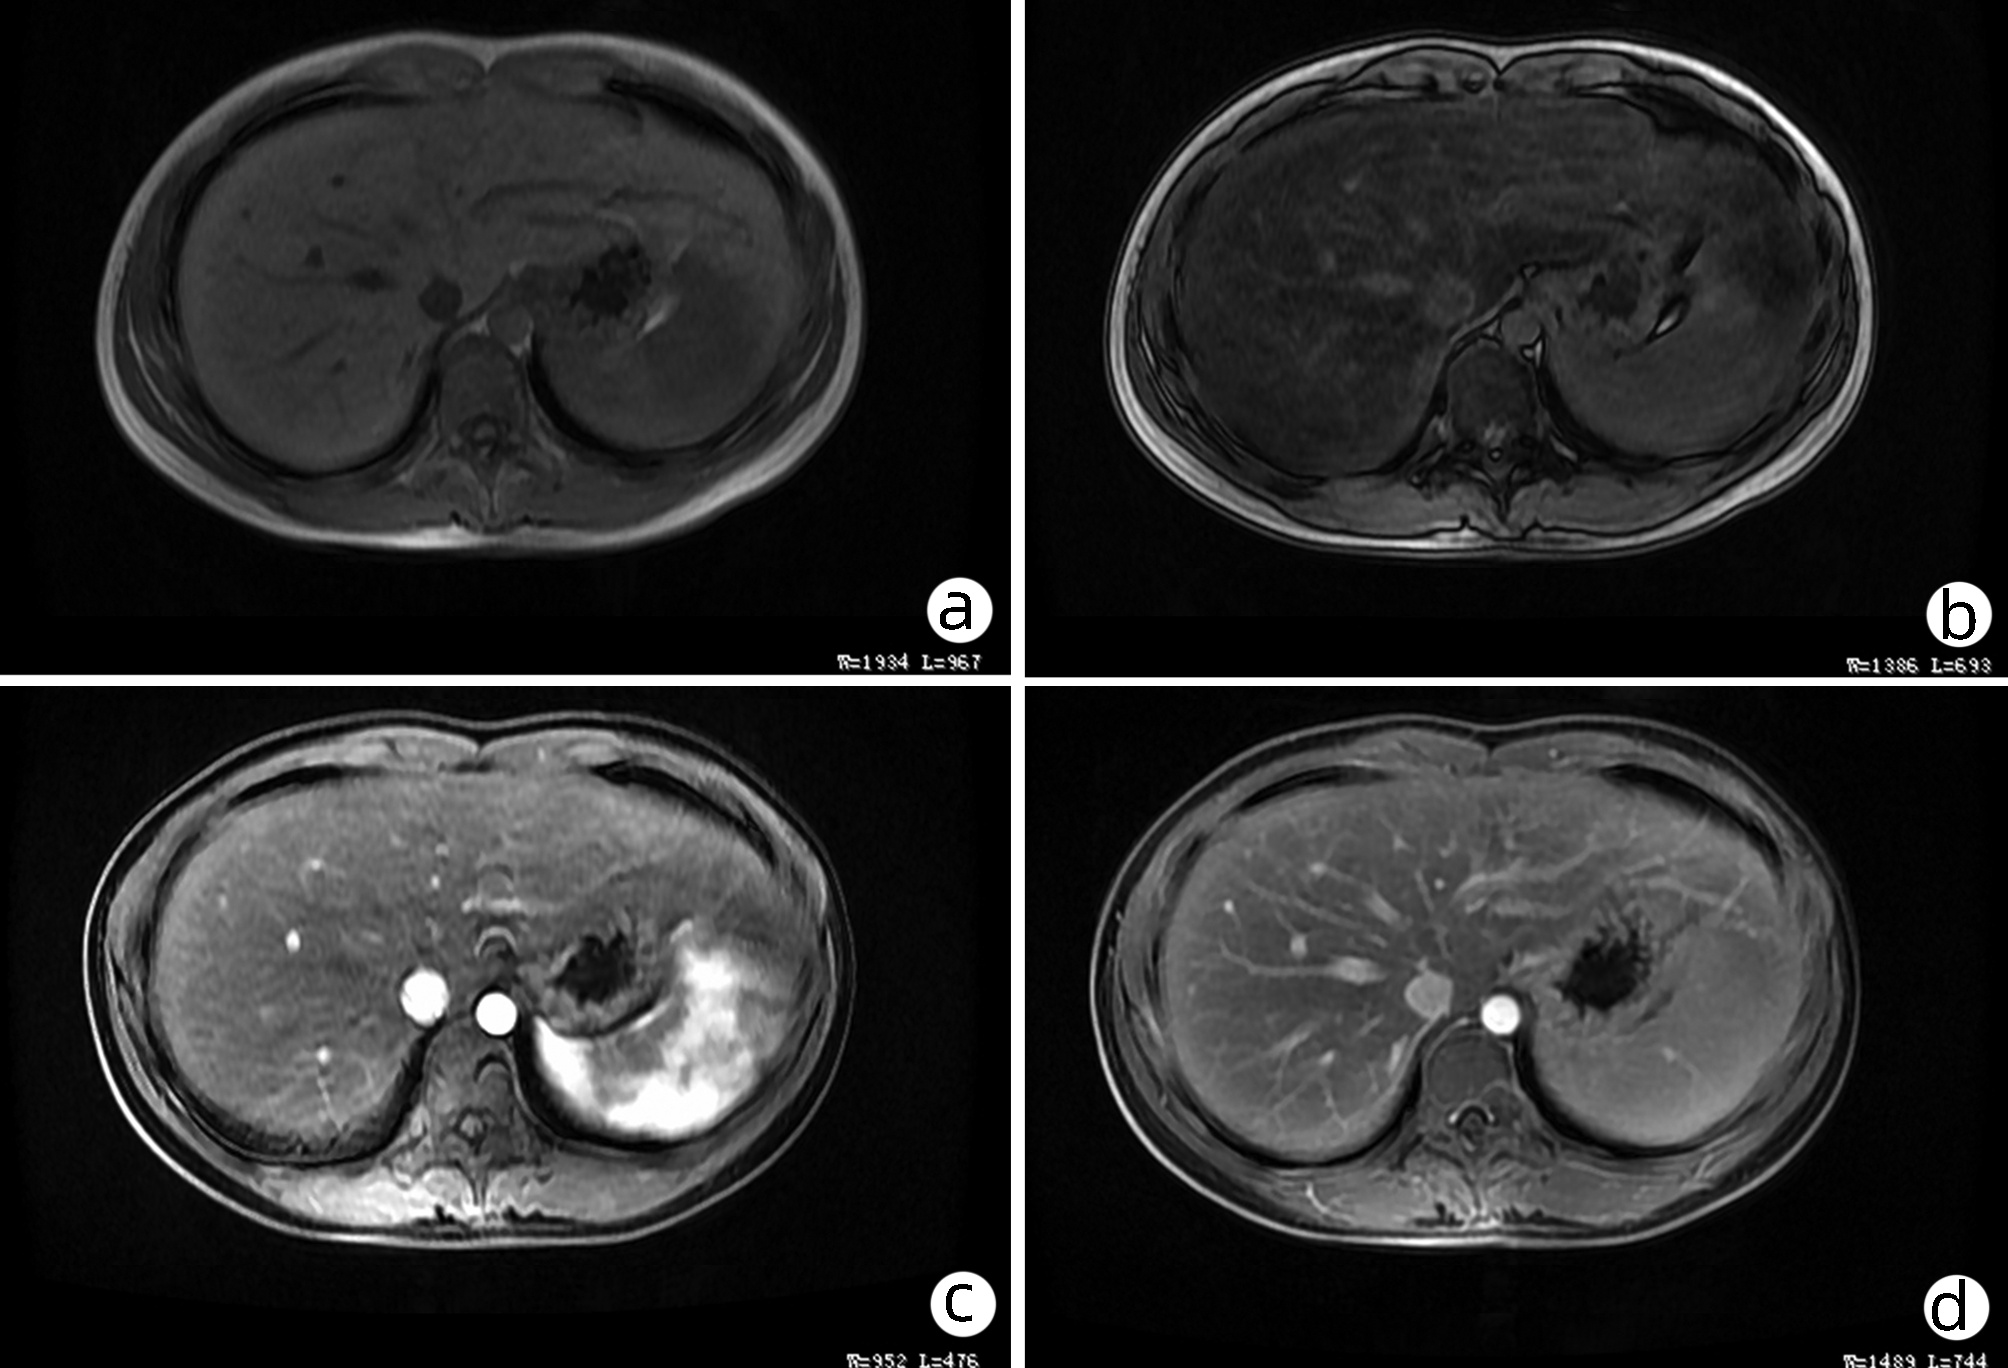

肝细胞癌合并胆管癌栓1例报告

2022, 38(8): 1872-1874. DOI: 10.3969/j.issn.1001-5256.2022.08.028

摘要(803) HTML (455) PDF (3665KB)(82)